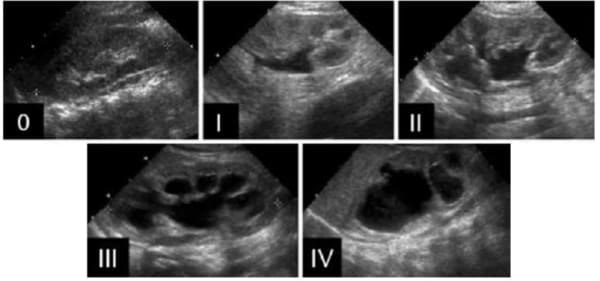

Classificação da Society for Fetal Urology (SFU)

0 - Rim normal

I - leve dilatação da pelve, sem dilatação dos cálices, parênquima normal

II – moderada dilatação da pelve, leve dilatação dos cálices, parênquima normal

III – acentuada dilatação da pelve e dos cálices, parênquima normal

IV – acentuada dilatação da pelve e dos cálices, redução da espessura do parênquima